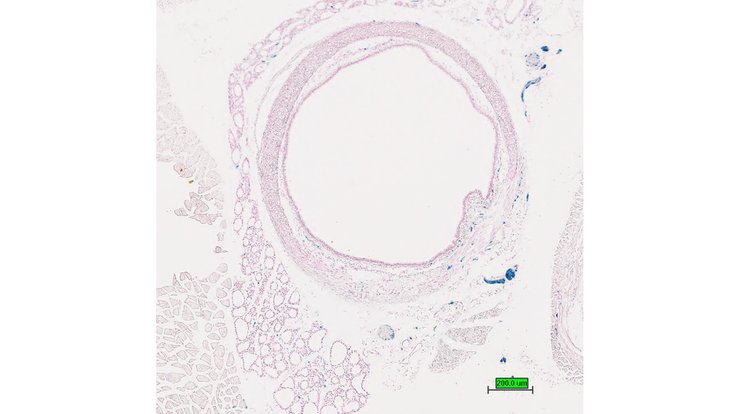

TS28: bladder Present UC Davis_1876062

Specimen UC Davis_1876063: postnatal adult; Kcna1tm1.1(KOMP)Vlcg/Kcna1+ (more )

Structure Level Pattern Image Note

TS28: bladder Present UC Davis_1876063

TS28: bladder Present UC Davis_1876137

Specimen UC Davis_1876138: postnatal adult; Kcna1tm1.1(KOMP)Vlcg/Kcna1+ (more )

TS28: bladder Present UC Davis_1876138